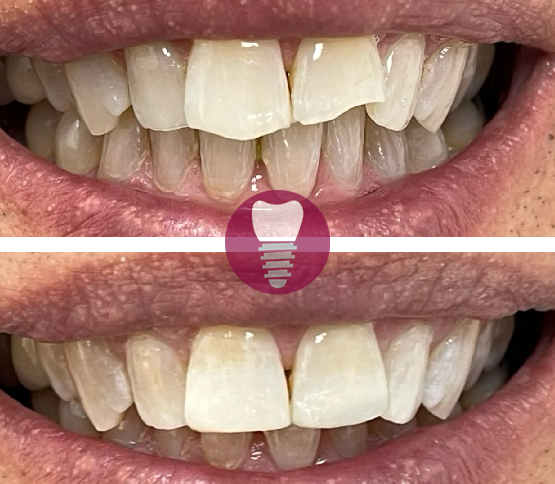

Este caso clínico muestra un tratamiento de restauración completa de la dentadura superior. Este tipo de intervención es ideal para pacientes que presentan una pérdida significativa de piezas dentales en la arcada superior o que tienen dientes gravemente dañados debido a caries avanzadas, desgaste, o problemas periodontales.

En este tratamiento, se emplea una prótesis sobre barra en implantes, proporcionando una solución estable y estética que permite recuperar la funcionalidad y la apariencia de la sonrisa. Este enfoque no solo mejora la capacidad de masticación del paciente, sino que también refuerza la estructura facial y restaura la confianza en su aspecto.

Gracias a la planificación digital y los materiales de alta calidad utilizados, el resultado es duradero y natural.